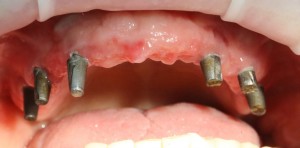

Хотите посмотреть, как на самом деле выглядит протез, изготовленный за 3 дня, и установленный на базальные импланты? Смотрите:

На протезе вы видите следы многочисленных коррекций и ремонтов. Зубы на нижнем и верхнем протезе в боковых участках из-за постоянных подточек, практически потеряли форму, не функциональны. И я объясню вам, почему такое происходит.

Дело в том, что со временем, по мере утраты зубов, у пациента перестраивается весь жевательный аппарат: изменения происходят в челюстных суставах, жевательных мышцах, челюстных костях и т. д. Тотальное протезирование на имплантах — весьма сложная штука, ведь врачу-ортопеду и зубного технику требуется определить такое соотношение челюстей, какое было тогда, когда у пациента еще были все зубы на месте. Это очень сложный, деликатный и важный этап диагностики. Умные доктора это знают, именно поэтому даже при небольшом протезировании используют различные виды функциональной диагностики. Здесь же ничего подобного не было. Работу максимально упростили — ну да, завышают протезы? Подточим! Не смыкаются? Наплавим! А то, что при этом чувствует пациент, что у него происходит с челюстными суставами и жевательными мышцами, как мне кажется, никто не задумывается.